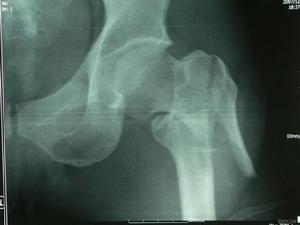

股骨轉子下骨折股骨轉子骨折系指股骨頸基底至小轉子水平以上部位所發生的骨折。亦為老年人常見的損傷。由於轉子部血液循環豐富,骨折後極少不癒合,故其預後遠較股骨頸骨折為佳。股骨轉子間骨折發生部位:大、小轉子之間,其內為松質骨,是股骨幹與股骨頸的交界處,承受的剪式應力最大。股骨矩:決定了轉子間骨折的穩定性位於股骨頸、乾連線處內後方的緻密縱形骨板前緣與股骨上端前內側骨皮質的相連後緣與股骨上端外後側相連 上極與股骨頸後側骨皮質融合下極與股骨幹後內側骨皮質融合。

單純轉子下骨折多見於年輕人,多由較大的直接暴力引起,不少病例骨折為粉碎性。而與轉子間骨折伴發的轉子下骨折可發生在骨質疏鬆的老年人,可因平地摔跌等較輕外傷引起。

轉子下骨折後,近端受臀肌,髂腰肌和外鏇肌群的牽拉而呈屈曲、外展、外鏇移位,遠端則受內收肌群和下肢重力的影響而向上、向內、向後移位。

間接暴力:跌倒時,身體發生鏇轉,過度外展或內收位著地;直接暴力:側方著地,大轉子直接撞擊;病理性骨折:骨的囊性病變;據股骨矩是否完整分為穩定性骨折:股骨矩完整;不穩定性骨折:股骨矩不完整。

傷後局部明顯疼痛,腫脹、急肢內收,短縮畸形,局部出血較多,常伴有失血性休克,由於外力強大,應注意多發傷及複合傷。1. Seinsheimer分型 Seinsheimer根據骨折塊的數量,位置及骨折線的形狀提出分為5型。

外傷史,傷後局部明顯疼痛腫脹,伴傷肢內收、短縮畸形。骨折部出血較多,需防止失血性休克。外傷暴力較大者,應注意檢查有無多發性創傷。X線檢查,即能確診。

轉子區腫痛瘀斑,下肢不能活動轉子間壓痛,準子區出現疼痛,腫脹、淤斑、下肢不能活動,檢查發現轉子間壓痛,下肢外鏇畸形明顯,可達90度,有軸向扣痛,測量可發現下肢短縮。X線拍片可明確骨折的類型和移位情況。